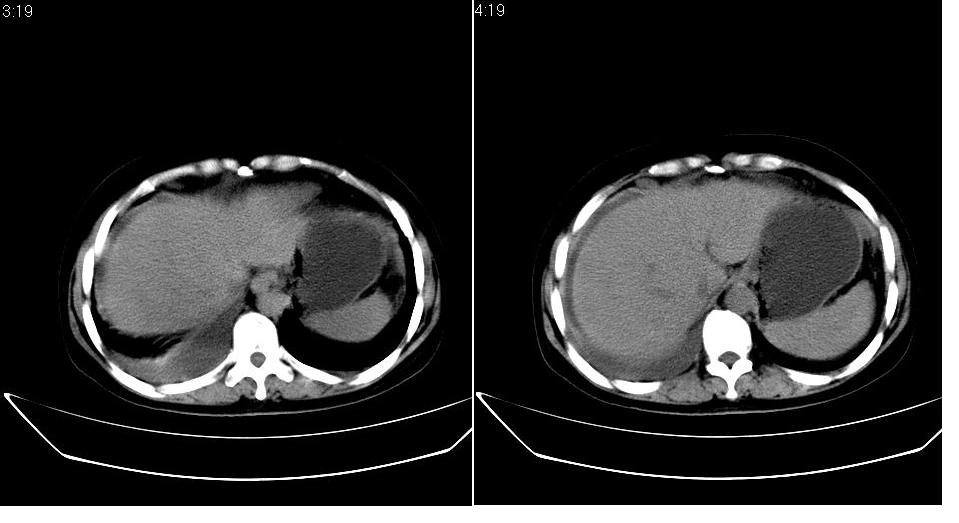

以下是引用zbp537在2009-1-19 14:09:00的发言:[br]从这个平扫图像上看,只能考虑:1、胸腹水。2、脾脏包膜下弧形高密度影,疑出血,建议复查。[br]既然腹水中有恶性细胞,建议行腹部ct增强扫描及胸部扫描。

以下是引用随光逐影在2009-1-19 15:47:00的发言:[br]1)不排除胃癌可能;建议行胃镜检查。2)腹水。3)右侧胸腔积液。

以下是引用jiangjing在2009-1-19 18:21:00的发言:[br]1 网膜污垢征---肿瘤网膜转移.2)腹水。3)右侧胸腔积液